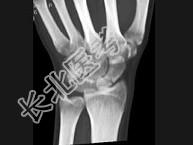

- 单项选择题男,21岁, 手部不慎摔伤,局部疼痛, 结合图像,最可能的诊断是 ( )

A、大多角骨骨折

B、小多角骨骨折

C、三角骨骨折

D、月骨骨折

E、舟状骨骨折